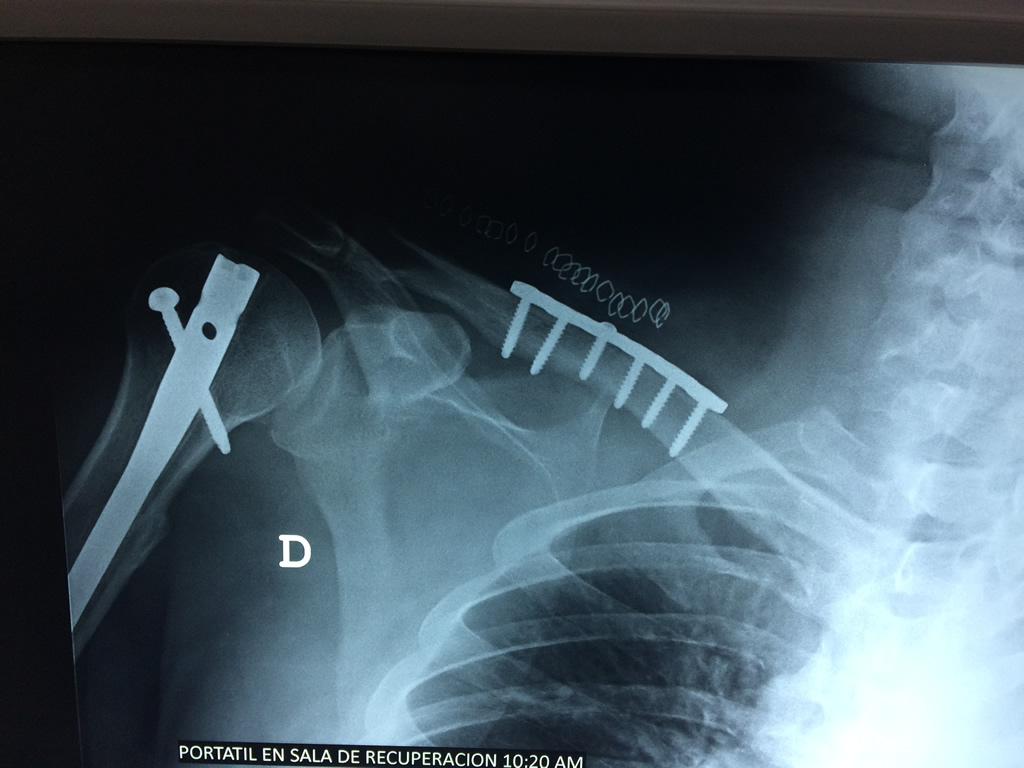

Húmero - Clavícula

La clavícula es un hueso largo, con forma de "S" itálica, situado en la parte anterosuperior del tórax. Junto con la escápula forman la cintura escapular. Se puede palpar por toda su longitud y se extiende del esternón al acromion de la escápula, siguiendo una dirección oblicua lateral y posterior.